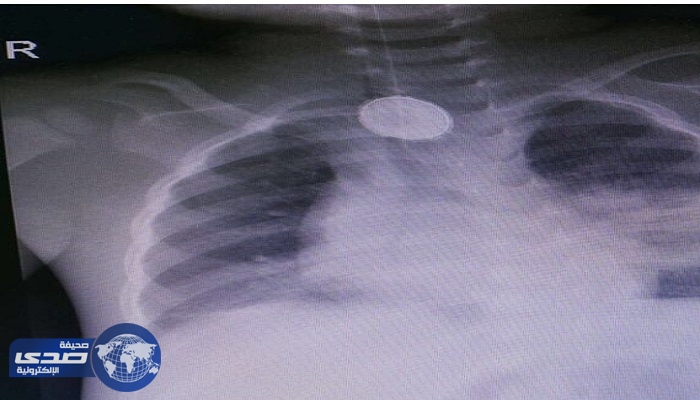

انقاذ حياة طفل في عملية نادرة بولادة مكة

منذ 8 سنة

2

3113